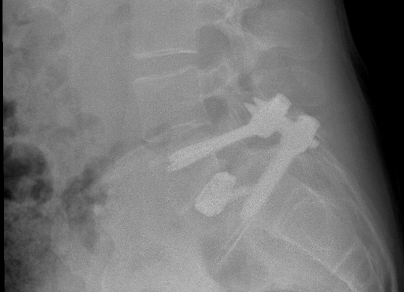

I am a 44-year-old man and have always been active in playing tennis, skiing, yoga, swimming, and many other activities. After having low back pain for more than 20 years, I had surgery in May 2024 with Dr. Huang at HSS, and now, at six months post-surgery, the pain is gone. Dr. Huang, along with Dr. Peter Connolly, performed spinal fusion at L5-S1 to correct high grade spondylolisthesis, and I would highly recommend them.

While my back had bothered me for quite some time, I found it worsening over the last five years, and, following a visit to my primary care physician and x-rays being taken, I was referred to a specialist for further imaging and consultation. The imaging revealed the grade 3 slippage of my vertebra at L5-S1, and I ended up meeting with six surgeons to determine the best course of action. Two of them recommended fusion from L4-S1 and the others including Dr. Huang recommended just the single level fusion. I picked Dr. Huang for the surgery because of his record of success and excellent reputation and that of the HSS.